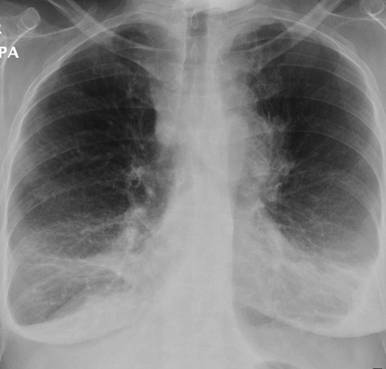

Figure 2. Chest X-ray showed mediastinal mass. |

Ultrasound and subsequent computerized tomography (CT) showed no gallstones but CT showed liver lesions which were reported initially as hemangiomas. On the 9th day of admission she developed swollen left upper limb. At that stage the radiology imaging were reviewed at the radiology multidisciplinary team meeting and her chest X-ray was compared to the previous one of two months which showed significant mediastinal widening and chest CT was suggested and showed extensive mediastinal disease and left internal jugular vein thrombosis and compression of left subclavian vein (Figures 1-4). The radiologist suggested lymphoma as the primary malignancy; however, the bone marrow biopsy showed a cellular marrow extensively infiltrated by a high-grade malignant tumour composed of small cells with scanty cytoplasm. Numerous mitoses were seen. Immunocytochemistry demonstrated a strong positive reaction for CD56 and bcl2, while a focal positive reaction was seen for bcl6. Perinuclear dot positivity was seen for MNF116. A negative reaction was seen for CD79, CD20, CD34, CD23, CD10, CD5, CD3 and cyclin D1.